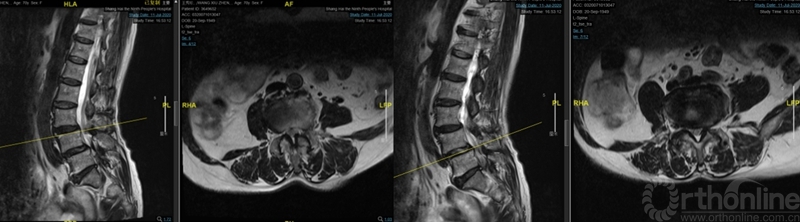

图3:术前核磁:腰3-4、4-5椎管狭窄

术后麻醉清醒后出现急性腰椎管狭窄症状:双足屈伸活动无力伴有麻木,以术前对侧无症状侧的左侧肢体为重。核磁显示:近端减压交界区硬膜囊成角和卡压,硬膜囊向右侧椎管减压侧漂移(图6、7)。

图6:第一次术后核磁:近端减压交界区硬膜囊成角卡压

图7:术后核磁:硬膜囊右侧减压侧椎管漂移